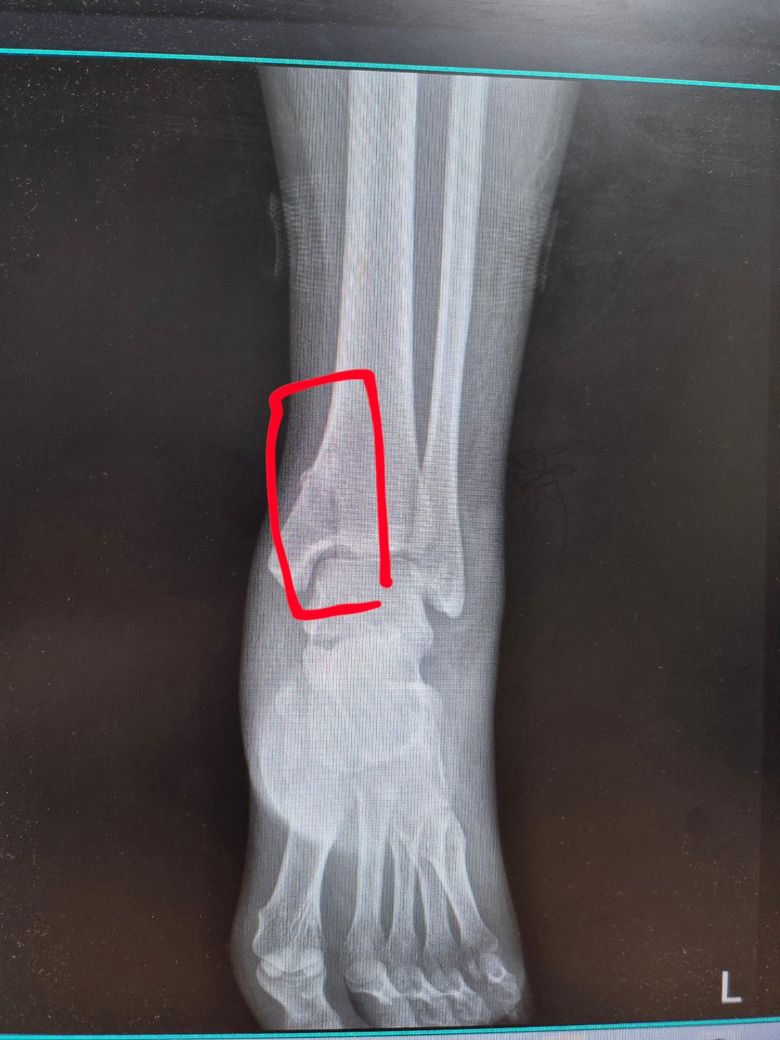

4월 16일 운동하다 다쳤고 밤이라 4월 17일 병원 가서 내측 복사뼈 골절 진단받았습니다.

붓기가 너무 심해서 1주일동안 고정시키고 상태보자고 했고 4월 24일 비수술 하기로 하면서 통깁스 시작했습니다. 6월 5일 6주간의 통깁스 마치고 2주 동안 반깁스 붕대로 했는데 6월 19일부터 붕대대신 벨크로로 변경하자 하셔서 변경했어요.

아래 사진은 6월 19일 찍은 사진입니다

• 1번 째 사진

현재 엑스레이 상으로 내측 복사뼈의 골절부는 어느정도 유합된 사태로 보이고 정형외과에서도 반깁스에서 벨크로로 전환을 권한 것을 보면 점진적 체중 부하를 시작해도 괜찮은 회복 단계로 판단됩니다!